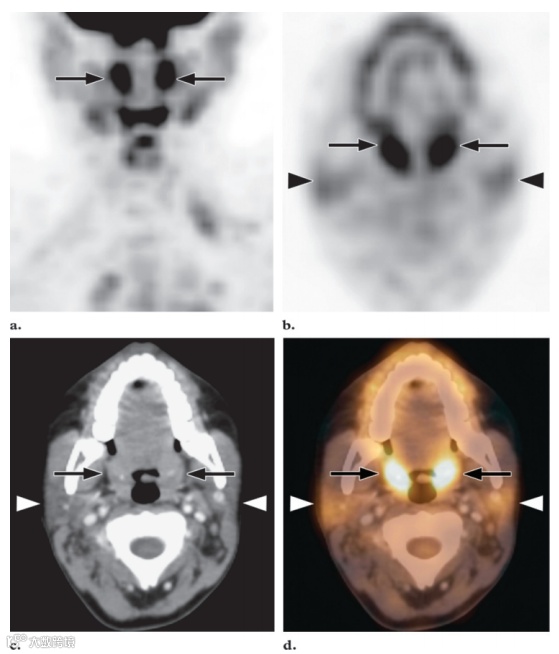

图2. 最大强度投影 (MIP) FDG PET 图像 (a) 和横向FDG PET (b)、CT (c) 和融合PET/CT (d) 图像显示正常扁桃体中有明显且对称的摄取 (箭头) 以及腮腺中有双侧轻度摄取 (b-d中的箭头) 。

最强烈的FDG活性存在于正常的大脑皮层和基底神经节中,因为大脑依赖糖酵解代谢作为能量来源(图1)。大脑代谢可能占整个空腹状态下的身体代谢的20%。大脑的总吸收量约为注射剂量的FDG的6%。由于韦氏环淋巴组织的生理活动,腺样体、扁桃体和舌根通常会出现轻度至中度的摄取。然而,在韦氏环中可以看到明显的强烈摄取(图2),尤其是在儿童中,因为这些淋巴组织的生理活性很高,在6-8岁达到峰值,此后逐渐减弱。在儿童体内这些区域的正常FDG摄取并不一定意味着有疾病。通常情况下,生理性扁桃体和腺样体摄取的对称模式有助于识别这种正常变化。软腭也可显示强烈的放射性示踪剂摄取。唾液腺的摄取情况各不相同,但通常为轻度至中度(图3)。有研究报告称,约51%的患者腮腺有轻度至中度摄取,腮腺高度摄取约14%。颌下腺和舌下腺的摄取情况各不相同,阳性率分别为53%和72%。化疗或放射治疗后也可见唾液腺摄取量弥漫性增加。由于近期手术或放射治疗后出现急性炎症,唾液腺对FDG的摄取可能不对称。然而,放射治疗最终可能导致患侧摄取减少。